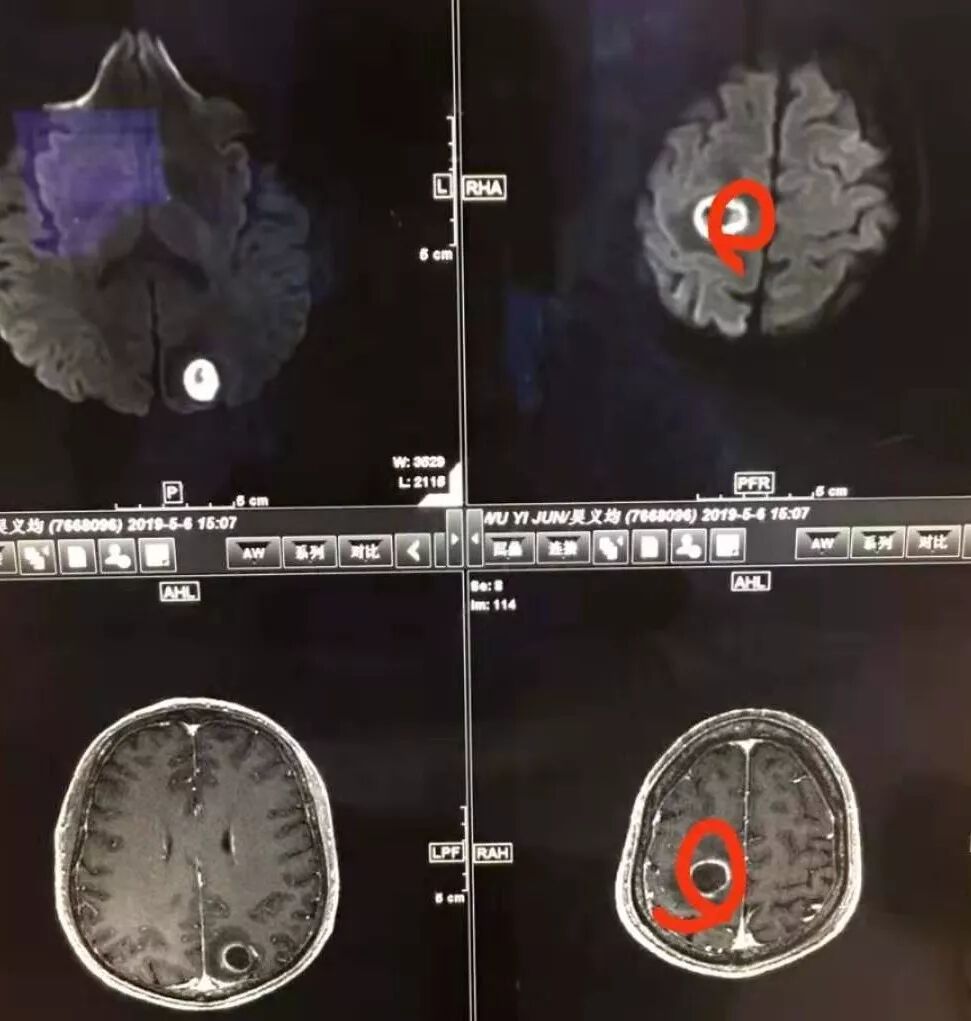

脑内的像隐球,肺内的像肺克,脑脓肿DWI腔内信号不够高,可能是隐球,但是也不能完全除外恶性。

右肺下叶见不规则软组织影,边缘不清,内夹杂气体,背段支气管未见明显阻断,增强扫描下叶病灶内见类圆形低强化区,其边缘光滑,见低强化区壁,颅脑左侧枕叶及双侧顶叶见多发长T1长T2信号,T2高信号内见类圆形异常信号,壁呈低信号,DWI环形壁未弥散受限,内容物弥散受限,周围为水肿区,增强扫描呈多发环形强化,考虑血源型感染,颅内及右肺下叶脓肿形成

脑内右侧顶叶病灶与其它脑内病灶不一致,壁弥散受限,内容物弥散低信号,转移瘤不能排除,其它脑内病灶支持脑脓肿

肺内病灶符合脓肿,颅内病灶几个表现不一样,多数脓腔弥散受限,壁不受限制,但有一个表现跟其他不同,内部不受限,壁弥散受限

多数薄壁,脓腔弥散受限是典型脑脓肿;右侧额叶的厚壁,壁受限,表现跟其他完全不一样,很是疑惑

颅内部分病灶是环形受限,中心没有受限,不支持脓肿

脑部病灶DWI受限,脓肿,中间也有受限,DWI第一,第二张图都是中间受限,第三,四是周围受限

DWI值对鉴别脑脓肿与囊性脑转移瘤有重要意义。包膜期脑脓肿其内容物主要为炎症细胞、微生物及蛋白质,其黏稠度相对较高,水分子弥散受到限制,DWI表现为均匀高信号。转移瘤囊变区主要以浆液性坏死物为主,其黏稠度相对较低,水分子扩散速度相对较快,DWI表现为低信号

脑脓肿和囊性脑转移瘤的鉴别点就是粘液(结合水)浆液(自由水)的鉴别

颅内环形的高信号,但是可以发现这个的DWI环是厚的,但是增强扫描的环是非常薄的,如果是肿瘤的,就是壁的弥散受限是肿瘤细胞的话,那么他强化的环应该跟DWI的环的厚度是一样的,所以这个环形的低DWI高信号应该是脓肿。而且就是关于这个脓腔壁的,就是脓腔的外壁是非常模糊的,而内壁还是相对光整,环不是很完整。下面一个图,没有给到,DWI上可以看到沿着破溃的脓肿壁向外侵出去的感觉,如果是环形转移的,那么它的那个内壁是更加不光整,而外壁是相对比较清楚一些的。

这个颅内病灶增强扫描的无强化区范围与DWI高信号范围是一致的,所以还是脓腔内受限,至少时期不那么典型,不是纯粹的高信号,DWI是厚层、增强是薄层;而且扫描角度也不一样,所以无法完全对上

3.脑内多发混杂信号病灶,显著长T1、显著长T2信号为主。注意TW1及TW2均显示环形等密度影(这在转移瘤是非常罕见的)且出现相应的环形强化。中央液化区DW扩散受限以及周边广泛水肿等,都符合典型多发脑脓肿改变。